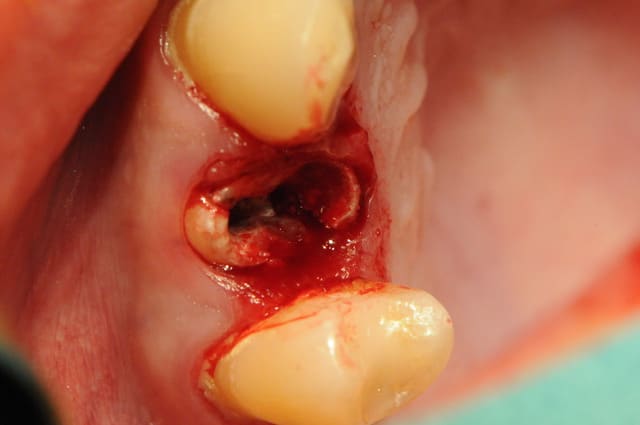

Tiens pour agrémenter! Cet Après midi une extraction implantation. Je n'ai pas oser la mise en charge immédiate si certains l'aurait fait lachez vous.

J'ai fait sauter la table vestibulaire exprès car je ne vois pas comment elle aurait pu etre vascularisée et à part me faire un séquestre osseux et des ennuis j'ai reconstruis.

Regardez les images;

Si certains n'auraient pas extrait argumentez pour traiter en palatin et la felure englobé par le granulome m^me si ce n'est pas mis en évidence sur le scan.

En plus vous voyez le nouvel implant Leone et son indication majeure, c'est vrai que sa mise en place est super aisée, surtout comme celà en palatin.